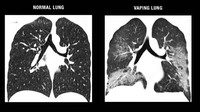

Begini perbandingan paru-paru sehat dan vapers. Pada vapers, terlihat kondisi parunya sudah memiliki bercak, pertanda kerusakan yang parah.  (Foto: UW Health)